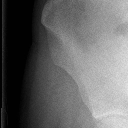

尿道外伤(14.68MB)

尿道外伤